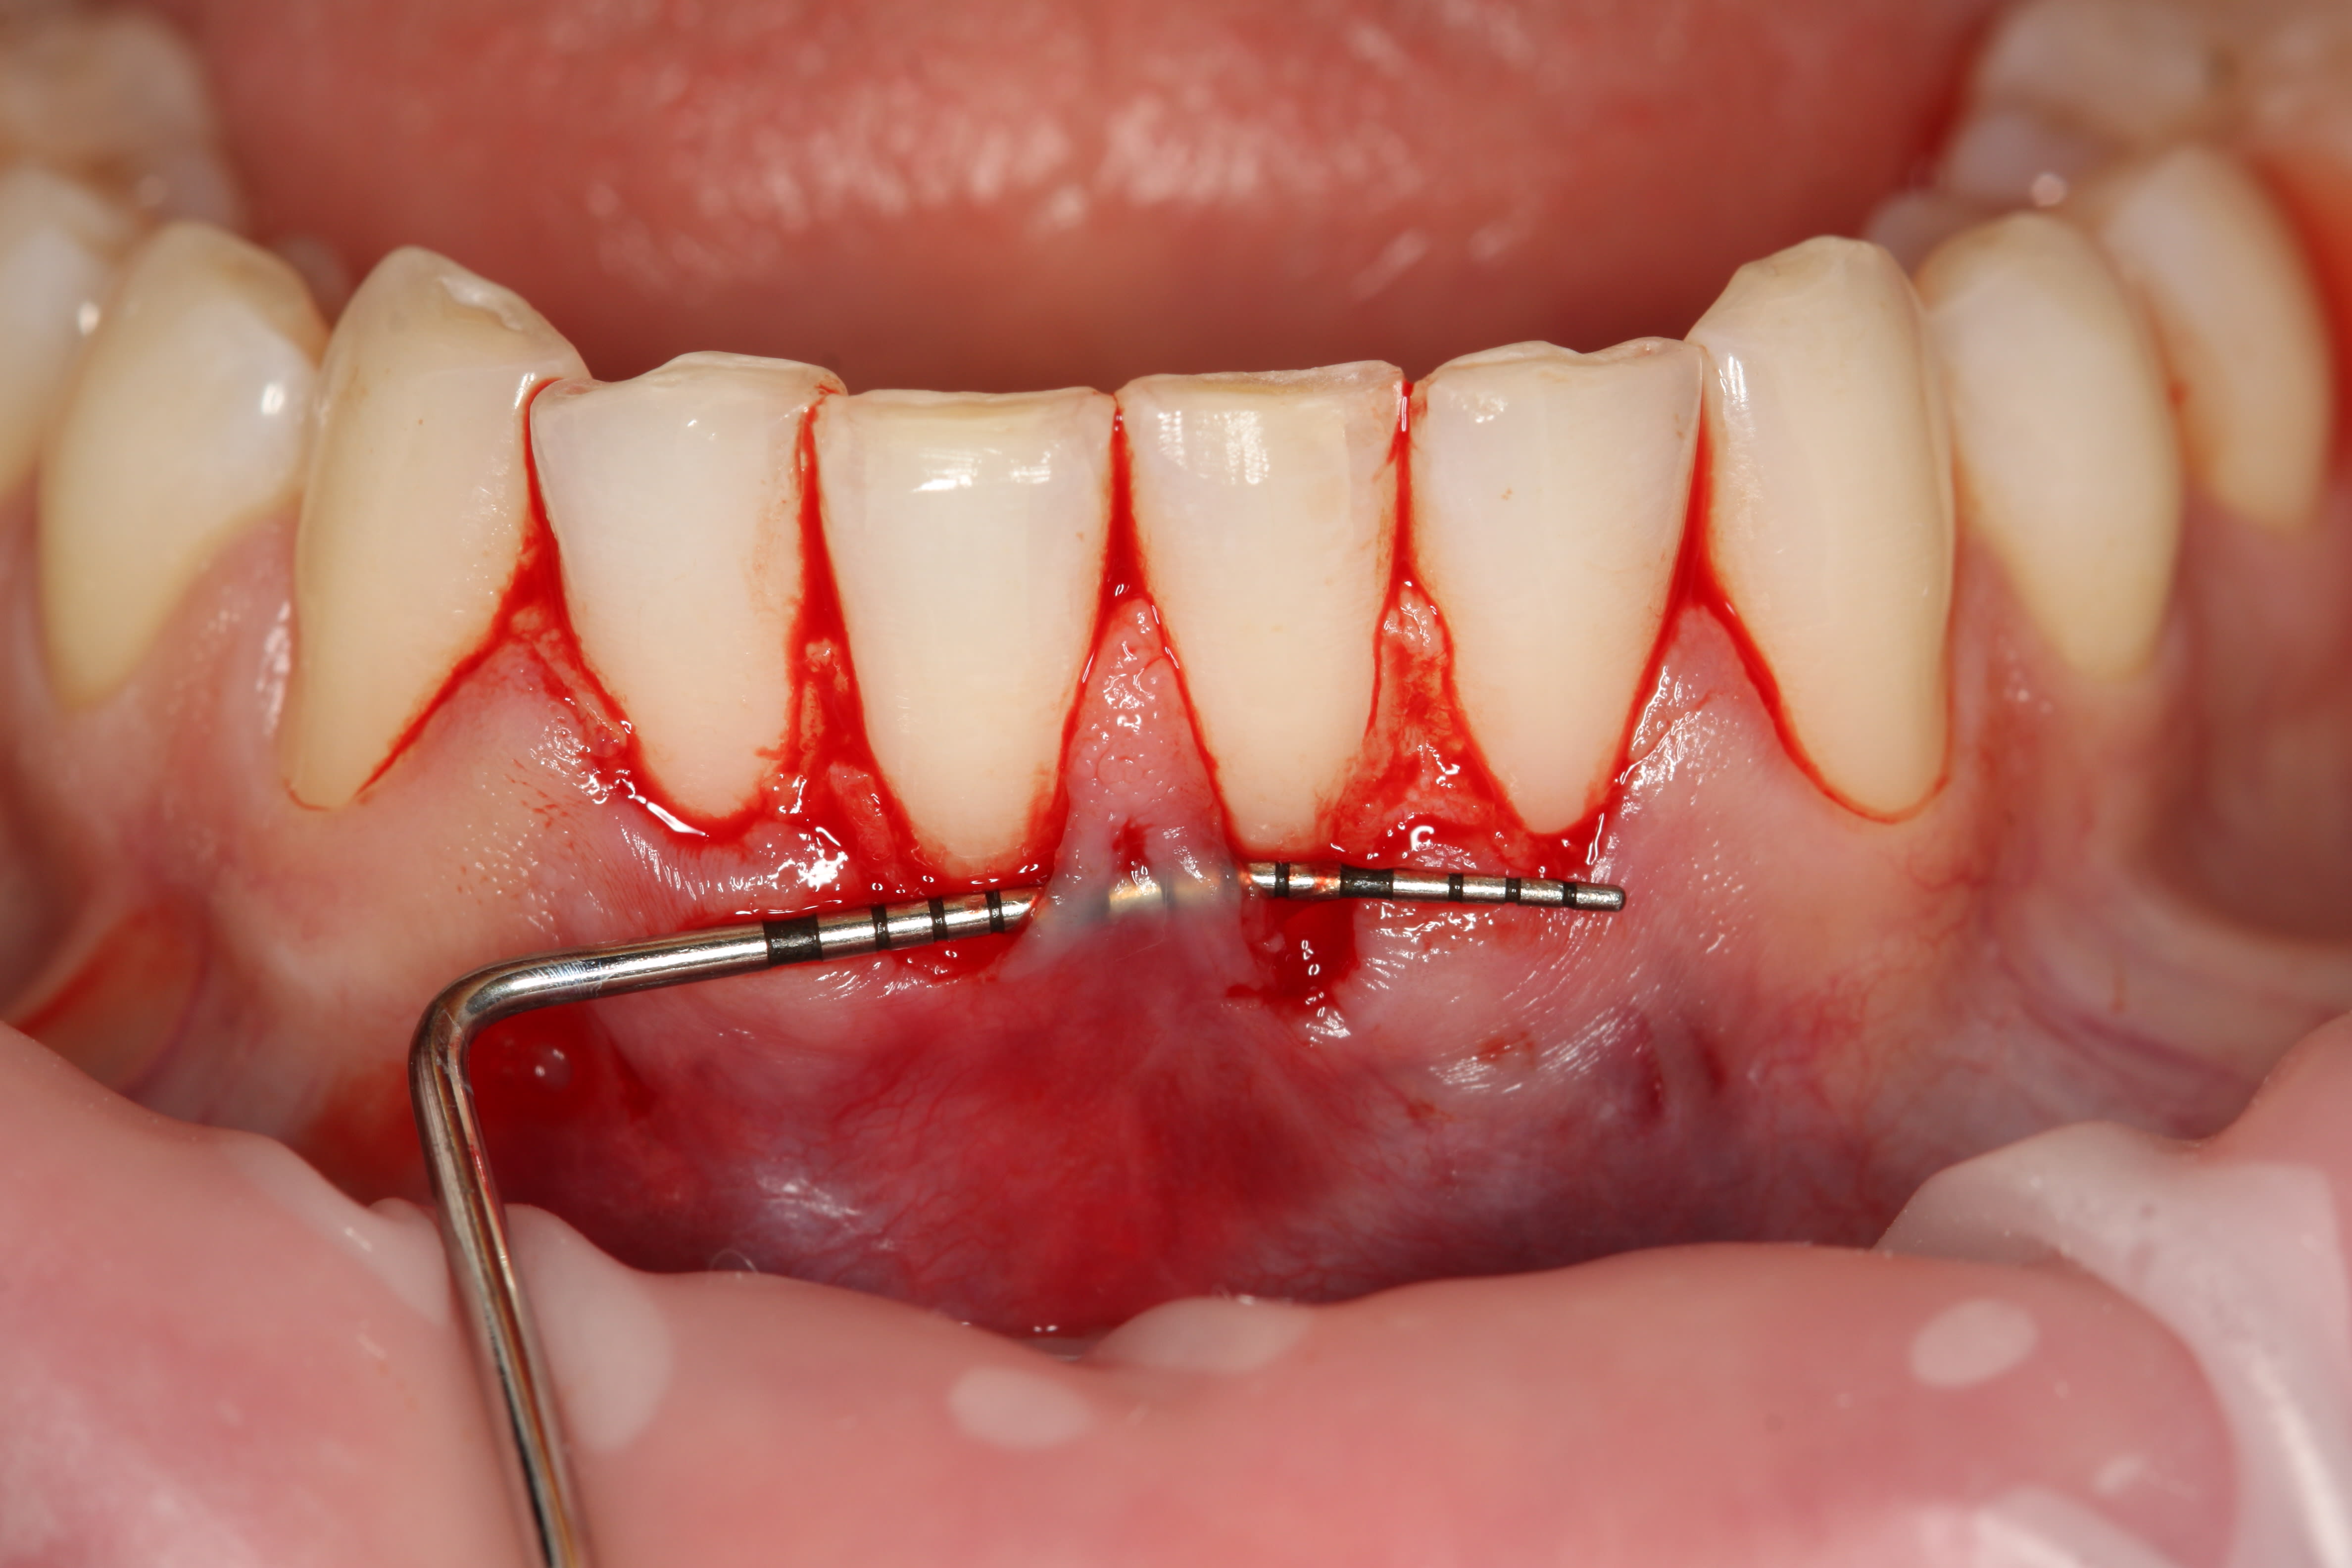

Cependant ici l'indication aurait plus été une technique avec une greffe épthélio-conjonctive en 1 ou 2 temps amha.

Car même si l'épaisseur de gencive attachée est plus importante que sa hauteur, ici c'est trop limite.

Une récidive sur 31m et 32m, voir 41m est à prévoir.

Je me pose plus la question sur le long terme sur les zones évoquées précédemment et le manque de gencive attachée et donc de tissu kératinisé.